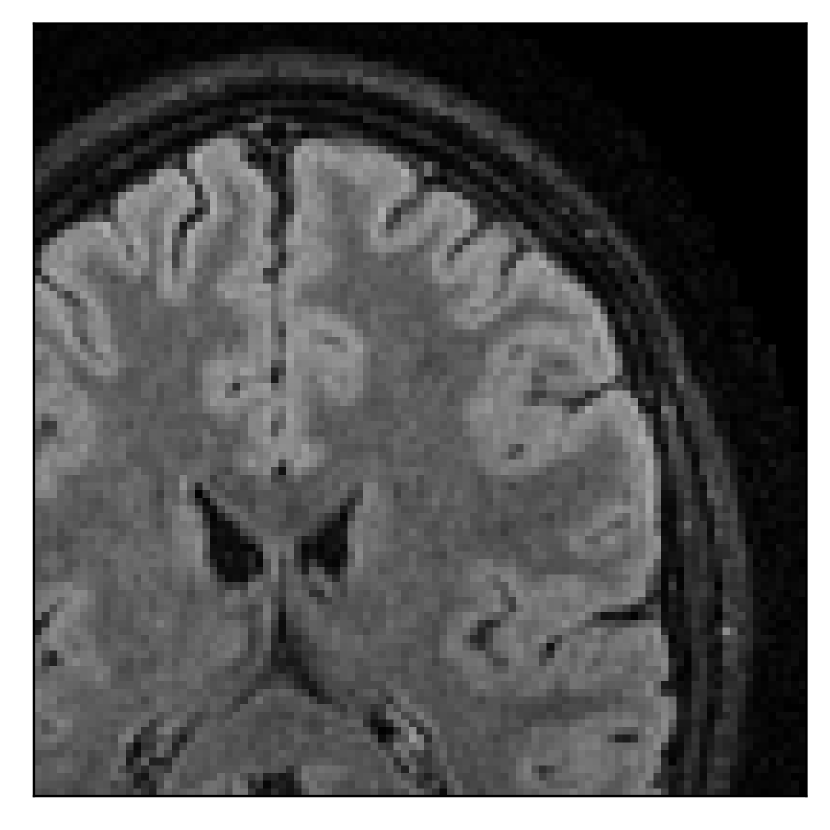

We consider three levels of motion corruption: (i) the volunteer moves once, (ii) the volunteer moves twice, and (iii) the volunteer moves five times. The volunteer is instructed to change its head position every time it is prompted to do so, and maintain that position in between instructions. We use T2-FLAIR-weighted contrasts as corrupted scans, with T1-weighted contrast as a reference (see Table 1 for further details). The corrupted acquisition employs randomized sampling.

| Section 3.1, Figure 2 | Sagittal | 23.94 | 27.95 | 0.7068 | 0.7936 |

| Coronal | 26.66 | 29.82 | 0.7653 | 0.8332 | |

| Axial | 25.40 | 30.16 | 0.7616 | 0.8490 | |

The motion-corrected full-volume scans were analyzed by a neuroradiologist with 16 years of experience. These were generally deemed of good radiological quality. The motion-related artifacts have been completely removed, and the results are quite close to the ground truth. In Table 3, we organized a more detailed qualitative analysis of the 3D results, geared toward a radiological assessment of the corrected scans.

| Section 3.1, Figure 2 | T2-FLAIR | Completely corrected | Some blurring | No additional artifacts | Good grey white matter differentiation |

4.1 Experiment 1: robustness test

We gather the results for the robustness test described in Section 3.1 (volunteer 1) in Figures 2, 4, and 6 for motion corruption mechanisms associated to one, two, and five changes of position, respectively. Furthermore, we juxtapose the corrected images with varying degrees of corruption in Figure 8. We observe that the proposed method consistently ameliorates the corrupted scan. The quality indexes based on PSNR and SSIM show only a modest decrease in correction quality as a function of motion complexity (Figure 8).